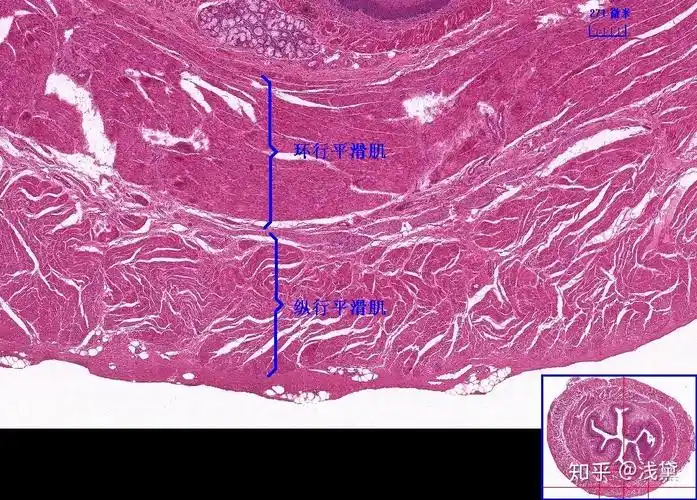

8.食管(纵行平滑肌,环形平滑肌,食管腺)7.